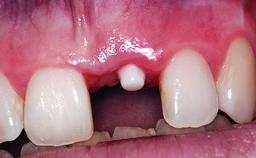

A 30-year-old patient presented at our clinic with a chief complaint of pain in her endodontically treated right maxillary central incisor (tooth 11) with a post-and-core and a fixed single crown. She had a very high lip line, a medium to thin soft-tissue phenotype, and a medium scalloped gingival contour. She also had high esthetic expectations because of her young age and beautiful smile. However, her expectations were realistic and she understood the risks of the treatment. At the initial clinical examination there was a slight mobility of tooth 11; no fistula was observed. The patient also had a single crown on the adjacent tooth 21. Both restorations were old and esthetically deficient. A digital periapical radiograph showed a very small periapical radiolucency, a thick intraradicular post, and no separation between root fragments.

Bone Augmentation Staged

Augmentation Materials Xenogenous|Membrane

Soft Tissue Grafting Simultaneous